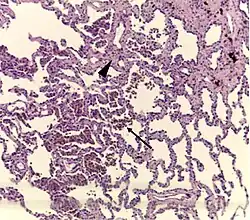

Respiratory bronchiolitis is a lung disease associated with tobacco smoking.[1] In pathology, it is defined by the presence of "smoker's macrophages".[1] When manifesting significant clinical symptoms it is referred to as respiratory bronchiolitis interstitial lung disease (RB-ILD).[1]

Diagnosis of respiratory bronchiolitis requires a correlation of clinical, radiologic and pathologic findings:[1]

- Pathologic: Lung biopsy with "smoker's macrophages" limited to distal airspaces and peribronchiolar airspaces, and minimal to absent peribronchiolar interstitial fibrotic thickening